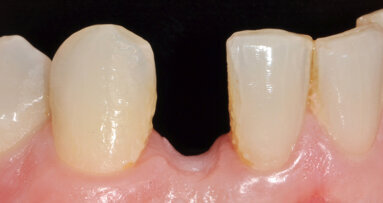

Wax-up umožňující vytvoření silikonového klíče.

Pacientka chtěla rovněž dosáhnout lepší estetiky svého úsměvu redukcí zjevných černých trojúhelníků mezi zuby 21 a 22. Ještě během akutní návštěvy byl pořízen otisk pro zhotovení wax-upu a technikou jednoho inkrementu byla zhotovena provizorní kompozitní výplň. Dříve, než bylo u pacientky přistoupeno k vlastní anatomické stratifikaci, byla u ní zahájena parodontologická léčba a provedeno endodontické ošetření zubu 11 (viz fotogalerie).